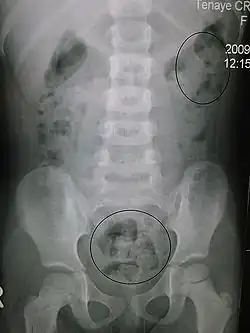

| The image shows the 4 parts of the colon (ascending, transverse, descending and sigmoid) and the rectum. Feces are transported along and stored in the rectum before excretion. | |

In order to correctly manage neurogenic bowel dysfunction it is important to accurately diagnose it. This can be done by a variety of methods, the most commonly used would be taking a clinical history and carrying out physical examinations which may include: abdominal, neurological and rectal examinations.[26] Patients may use the Bristol Stool Chart to help them describe and characterise the morphological features of their stool, this is useful as it gives an indication of the transit time.[27] An objective method used to evaluate the motility of the colon and help with diagnosis is the colon transit time.[28] Another helpful test to diagnose this condition may be an abdominal X-ray as this can show the distribution of feces and show any abnormalities with the colon, for example a megacolon.[16]